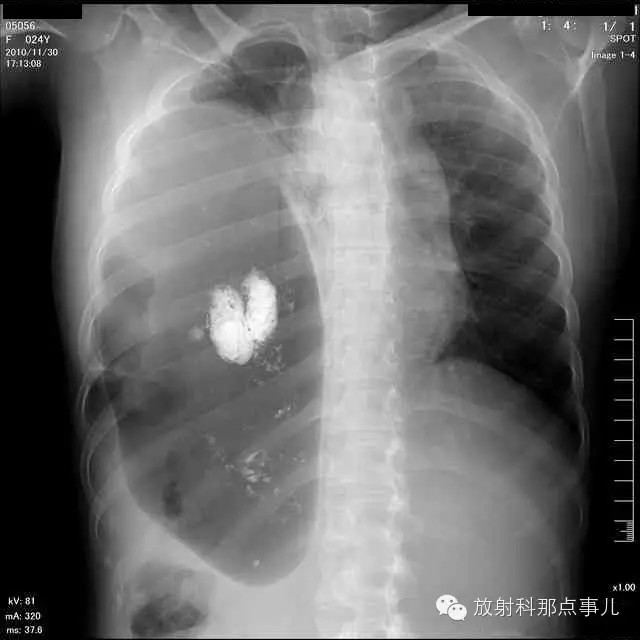

【病例学习】膈疝一例X线诊断

24岁,女性,腹痛渐加重并呕吐。

患者系顺产后18天产妇,产后感觉腹部疼痛不适,自认为正常反应,近两日因胸闷、腹部疼痛加剧伴呕吐来院就诊。

门诊腹部透视发现左侧胸腔巨大气液平面,为排除膈疝口服钡剂,但造影剂未见进入胃内。嘱住院,外科给予胃肠减压、补液等处理常规处理(未引流出明显气、液体)。5个半小时后再次检查,见少量造影剂进入消化道;为进一步了解情况,予泛影葡胺分别经胃管推注及口服,但均未进入胃内。当天进行外科急诊手术。

大部分胃、脾及横结肠均经过胸肋三角疝入左侧胸腔内,并见疝环形成。

考虑该患者因生产过程中腹压急剧升高,导致腹内脏器经膈肌缺损或薄弱部位进入胸腔内。